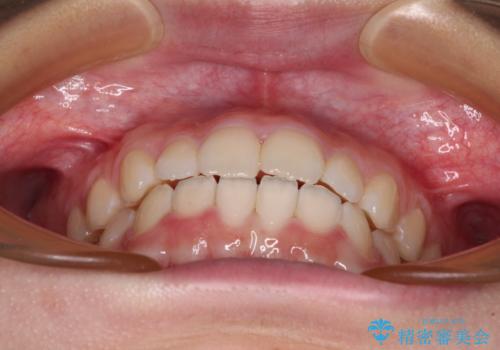

- 前歯のデコボコを気にして来院された高校生の患者様です。

捻れた前歯が前方に飛び出している点も気になっており、目立たない装置を希望されたため、インビザラインを用いて矯正治療を行うこととしました。

上下ともに少し捻れが残っていたため、治療の継続を提案しましたが、本人も親御さんも満足とのことで、治療を終えました。

捻れの改善により突出感も改善されました。